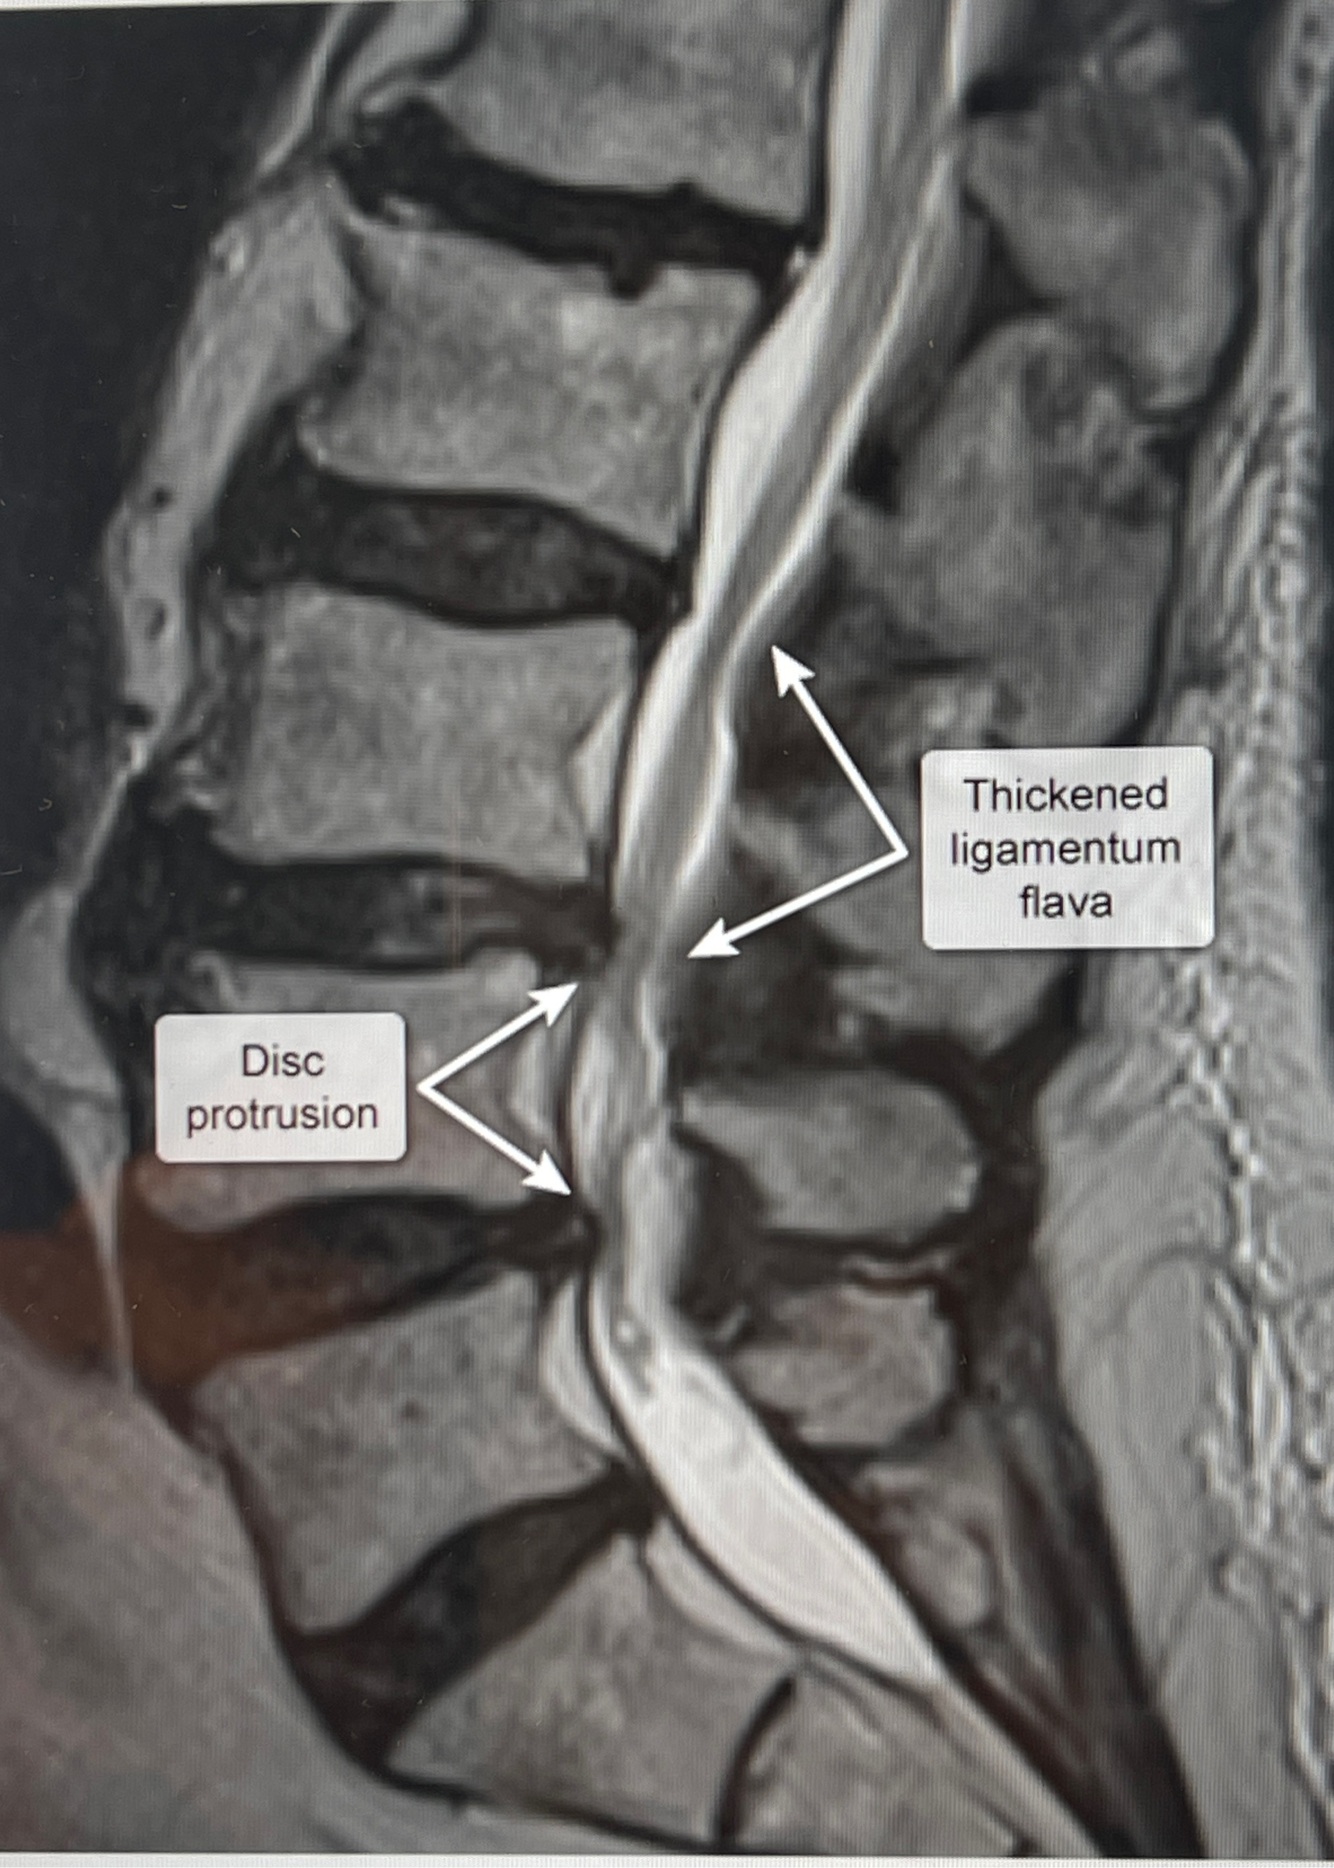

15

Q

A

How well did you know this?